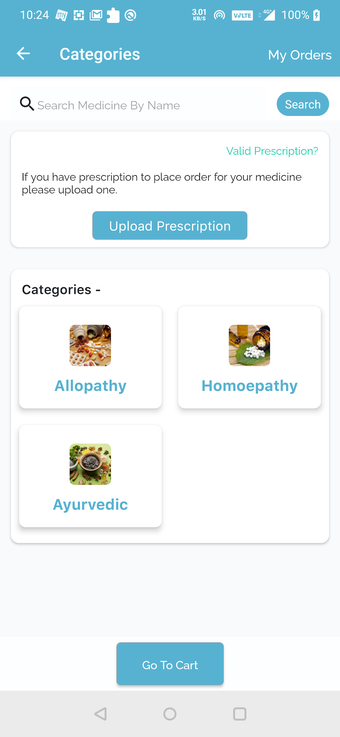

Możesz poprosić ich o wycenę kosztów leczenia lub recepty. Ponadto możesz skorzystać z usług apteki QuickObook. Jeśli pacjent nie ma ubezpieczenia zdrowotnego lub plan ubezpieczenia nie pokrywa kosztów leczenia, zostaniesz o tym poinformowany z góry.